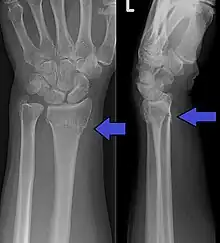

Colles fracture of the left hand, with posterior displacement clearly visible

Diagnosis can be made upon interpretation of anteroposterior and lateral views alone.[6]